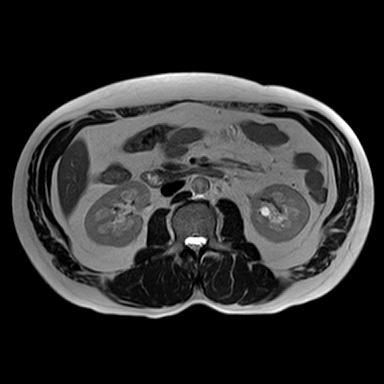

신장 양쪽에 혹이 있다고 하는데 (좌신, 등)

• 3번 째 사진

• 비뇨기과를 가시는 것이 맞고, 제공해주신 MRI와 초음파 소견을 종합하면, 양측 신장에 병변이 보이기는 하나 형태가 서로 다릅니다. 한쪽은 비교적 경계가 명확하고 밝게 보이는 병변으로 낭종 가능성이 우선 고려되고, 반대쪽은 내부 신호가 혼재된 형태로 단순 낭종 외의 병변 가능성도 완전히 배제하기는 어렵습니다. 다만 단일 컷 이미지로는 조영 증강 여부, 내부 구조, 혈류 평가가 제한되어 확정 판단은 불가능합니다.

임상적으로 중요한 기준은 단순 낭종인지, 복합 낭종인지, 혹은 고형 종양인지 구분하는 것입니다. 단순 낭종이면 추가 치료 없이 경과관찰이 원칙이고, 복합 낭종이나 고형 병변이면 추가 평가가 필요합니다. 이 구분은 조영증강 CT 또는 조영 MRI에서 보스니악 분류 기준으로 판단합니다.

현 시점에서 급하게 의심할 소견으로 단정하기는 어렵지만, 양측성 병변이므로 단순 낭종인지 확인은 반드시 필요합니다. 특히 40대에서는 우연히 발견되는 낭종이 흔하지만, 복합 낭종은 일부에서 종양과 연관될 수 있어 정밀평가가 필요합니다.